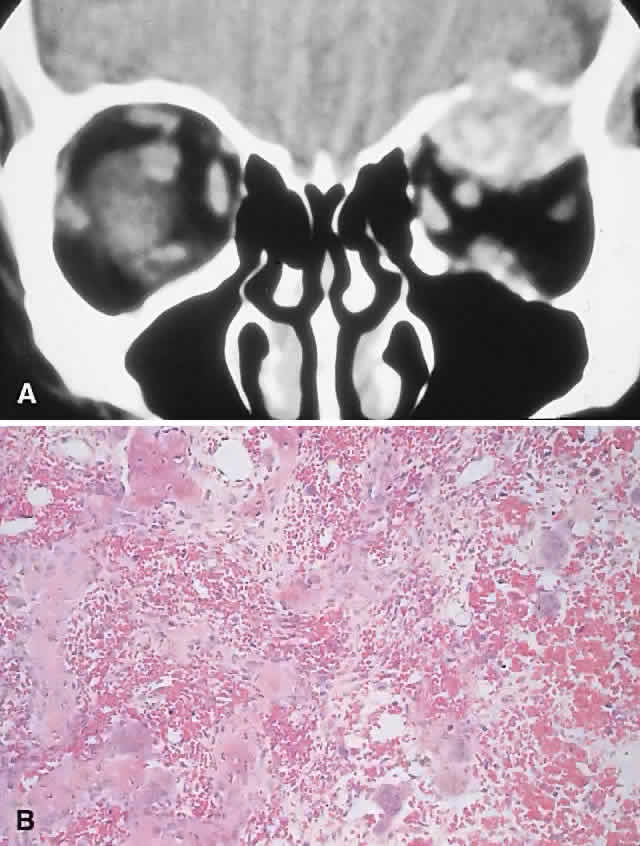

PRESENTATION. The site and the extent of disease are the major determinants of symptomatology. Facial asymmetry, proptosis, and globe displacement evolving over many years are the most common manifestations (Fig. 2). Nasolacrimal duct blockage, diplopia, nasal obstruction, malocclusion, raised intracranial pressure, and cranial nerve palsies also occur.25,28–30 Acute or subacute compressive optic neuropathy can arise as a result of intralesional hemorrhage, sphenoidal mucocele, or secondary aneurysmal bone cyst.31 A more chronic visual loss, although less commonly reported, may occur as a result of compression in the optic canal or at the chiasm. On occasion, a superimposed ischemic neuropathy in the context of chronic compression leads to an acute on chronic deterioration in vision.32

Fig. 2. A. A 20-year-old man presented with a longstanding history of left proptosis and facial asymmetry. B and C. Bone window CT scan showed extensive fibrous dysplasia involving the greater wing of the sphenoid in a sclerotic fashion and a more pagetoid appearance in the maxillary and ethmoidal regions. D and E. Dominant histologic features consisted of irregular trabeculae of woven bone in a fibrous stroma with minimal osteoblastic activity (E) surrounding the osteoid (hematoxylin-eosin; D × 20, E × 50).

This clinical spectrum is reflected in our experience of 10 cases. Changes in facial contour (7 patients), proptosis (7), globe dystopia (6), and decreased vision (3) were the major signs. Interestingly, seven patients also had pain, either localized to the orbit or described as a diffuse ipsilateral headache.

IMAGING. In the craniofacial bones, fibrous dysplasia tends to expand the bone, with thinning of the overlying cortex. The margins are poorly defined, and the dysplasia transgresses suture lines; the proportion of mineralized to fibrous tissue determines the degree of radiolucency. Most cases demonstrate a relatively equal mixture, resulting in a pagetoid appearance. Where the fibrous element is predominant, there may be cystlike areas; a preponderance of mineralized tissue, however, results in a homogeneous, sclerotic, “ground-glass” picture. Fries34 reviewed 39 patients with fibrous dysplasia of the craniofacial bones and found a pagetoid pattern to be most common (56%), followed by sclerotic (23%) and cystlike (21%) appearances.

HISTOPATHOLOGY. Macroscopically, fibrous dysplasia consists of gritty, white-to-pink tissue, often with blood or serous-filled cystic areas. Histologically, there is a fibrous background containing trabeculae of woven bone. The stroma has variable amounts of collagen, fibroblasts, and vascularity. There may also be myxomatous areas and secondary aneurysmal bone cysts. The curvilinear bone trabeculae take on a variety of configurations, including C or Y shapes (so-called Chinese characters). These trabeculae sometimes have irregular margins as a result of the attachment of collagen fibers arising in the stroma. Cartilaginous nodules as well as small foci of lamellar bone are occasionally seen, but the vast majority of lesions contain immature woven bone. At its periphery, fibrous dysplasia permeates normal bone, and there may be areas of reactive bone with more prominent lamellar bone formation and osteoblastic rimming. Sequential biopsies of fibrous dysplasia from childhood to adult life have shown that the histologic picture does not change with time.36